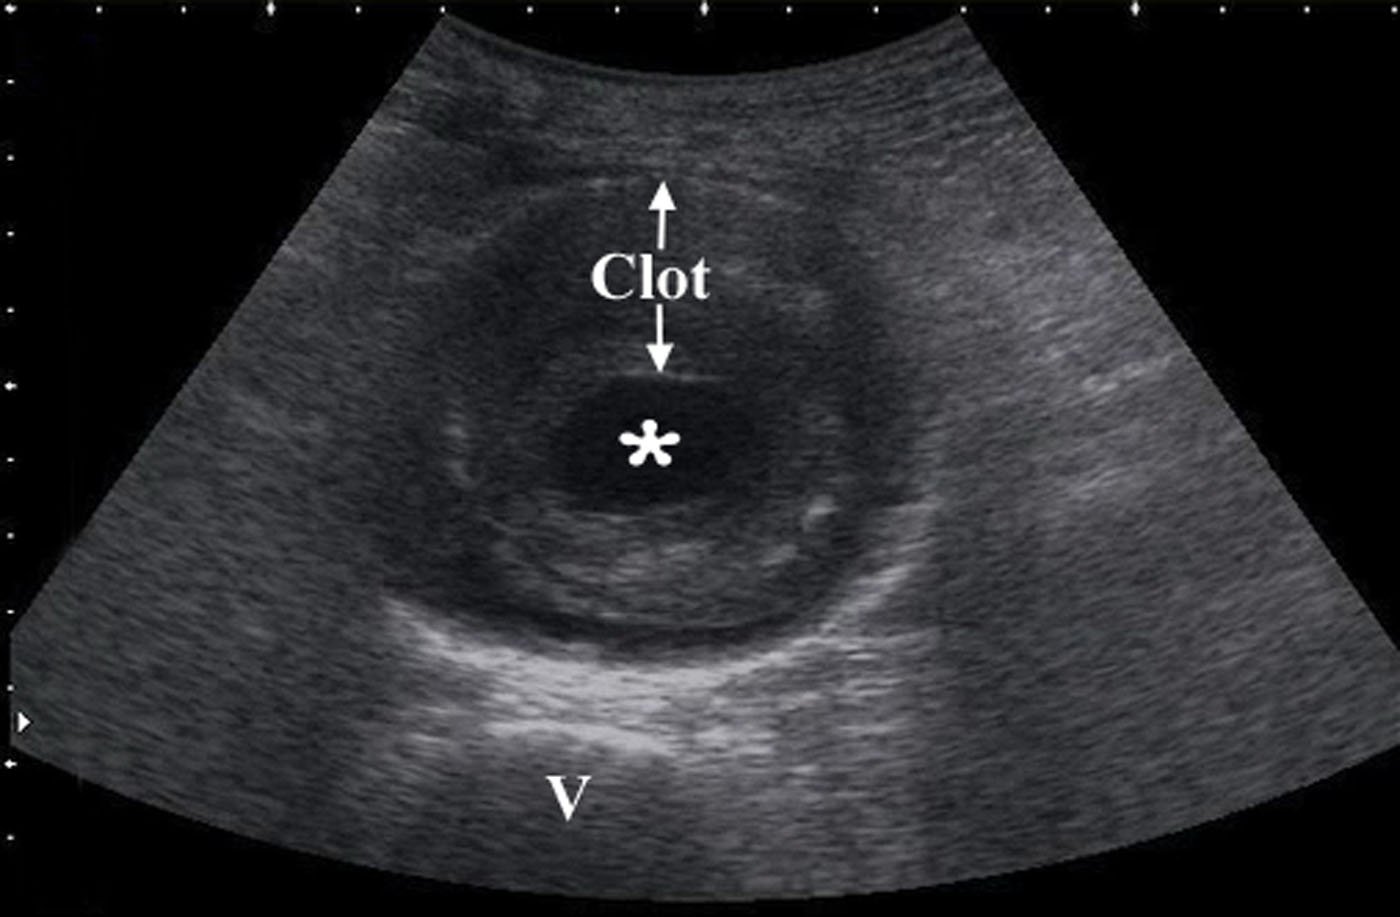

Ultrasound By Emergency Physicians To Detect Abdominal Aortic Aneurysms A Uk Case Series Emergency Medicine Journal

Sonoguide Abdominal Aortic Aneurysm